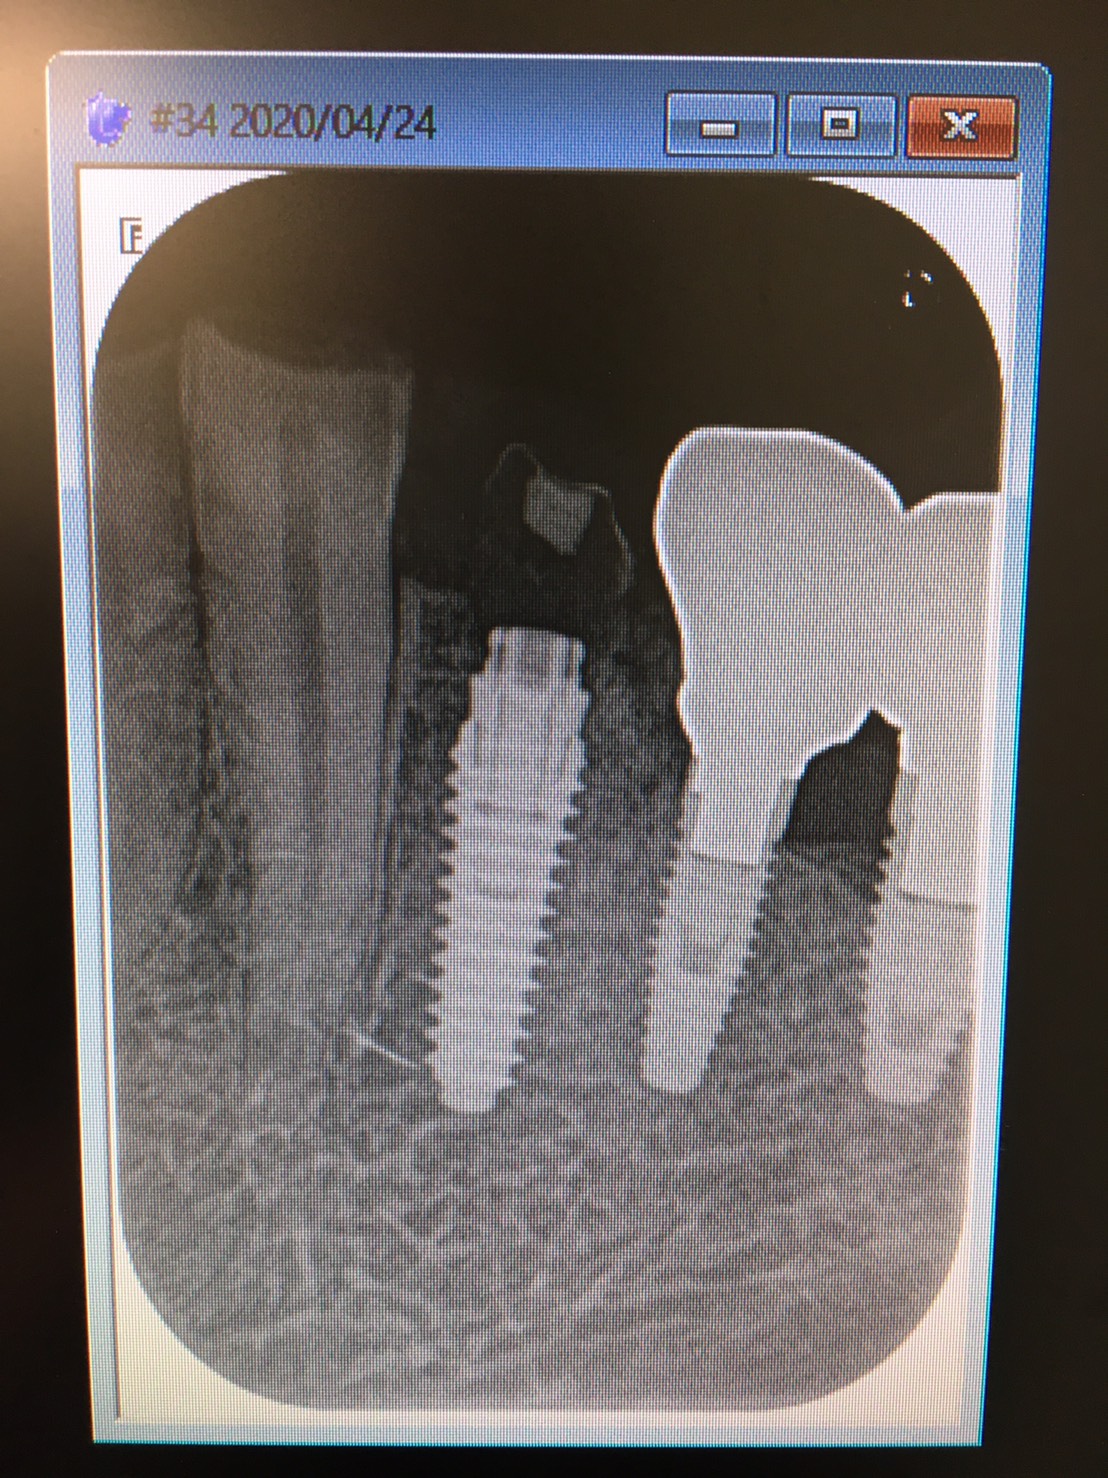

左下4番の抜歯と同時にインプラントの埋入オペをし、即時に仮歯を装着し噛めるようにする難易度の高いオペです。患者さんは2週間前にも右下に同様のオペをされた方です。

骨質を見極めたドリリングテクニックはいつもの様にスムーズに行われ骨との合着値も良い結果が出ています。